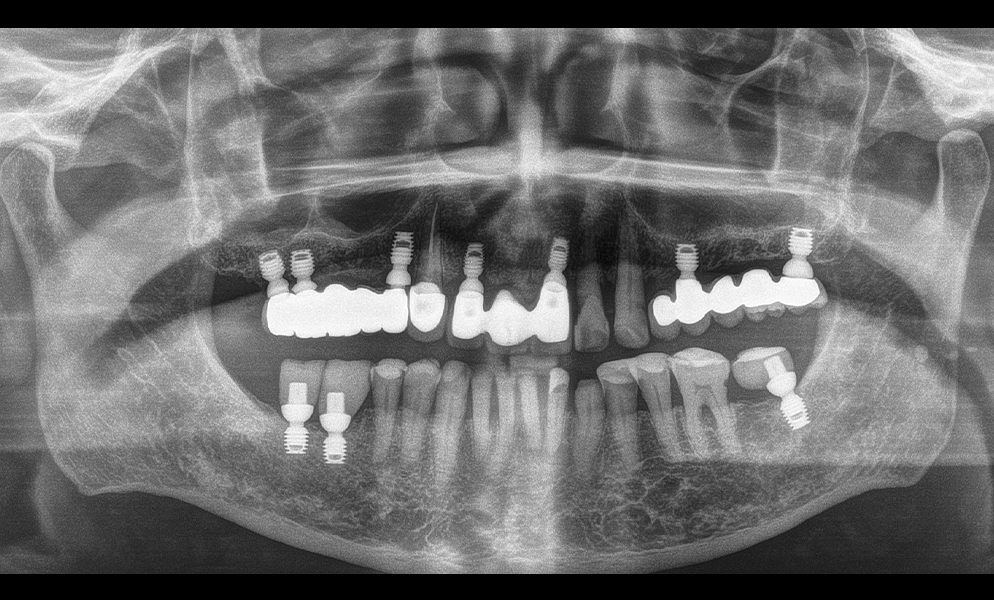

| Before | After |

![]() |

| Full-mouth reconstruction with short dental implant (Bicon, USA)-supported prosthesis | |